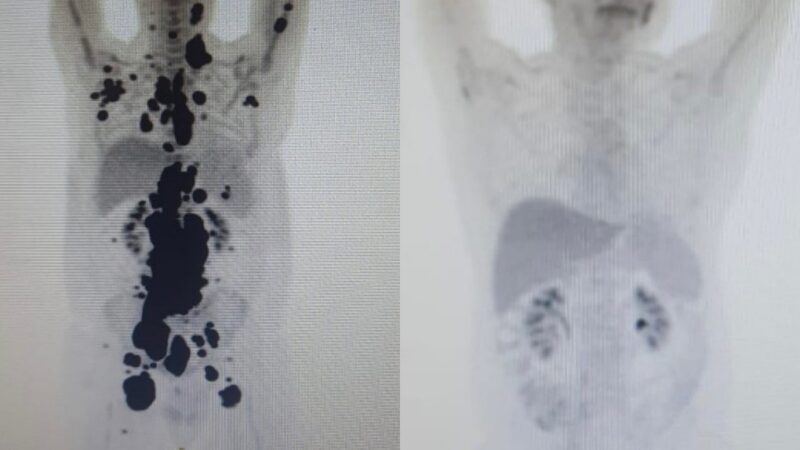

Paulo Peregrino, de 61 anos, é um dos casos mais recentes e emblemáticos. Diagnosticado com linfoma há 13 anos, ele estava prestes a iniciar cuidados paliativos quando recebeu a terapia em abril. Em apenas um mês, exames mostraram remissão completa da doença, surpreendendo os especialistas envolvidos no estudo.

O tratamento consiste na modificação genética das células T do próprio paciente, que são multiplicadas em laboratório para reconhecer e combater as células cancerígenas de forma eficaz. Paulo passou pelo procedimento no Hospital das Clínicas de São Paulo, sob supervisão do professor Vanderson Rocha, que destacou a rapidez e a intensidade da resposta ao tratamento, algo incomum e animador para casos avançados.